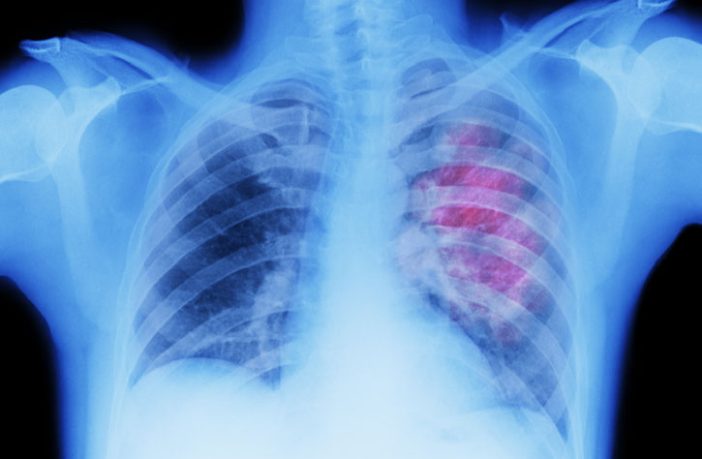

ويظل سرطان الرئة السبب الرئيسي لحدوث السرطان والوفيات في جميع أنحاء العالم. وفي عام 2022، تم تشخيص نحو 2.5 مليون شخص بالمرض.